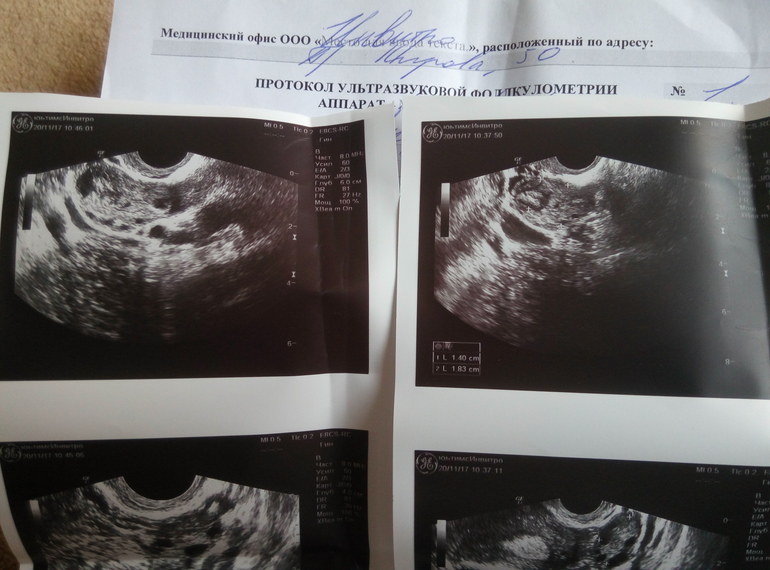

ФолликулометрияДевочки, может есть кто в узи разбирается хорошо? Что-то не понимаю как такое может быть. День цикла 22, овуляция обычно поздняя и на 17-22дц, по базальной темп О была на 15дц, заметила в этот день немного беж выделения, потом несколько дней был ЯБ, и позавчера очень резкую боль в левом яичнике(что совсем сбило с толку об овуляции), по узи: м-эхо 1,08см, форма овальная, структура однородная, контур ровный (во время узи сказала, что не очень однородной структуры) , оба яичника 6-8ф до 6мм, свободной жидкости сказала нет, но что написала в заключении- для меня загадка)) фотографию прилагаю, может кто поймет, что написано?))

Желого тела она не увидела, сказала цикл ановуляторный. Фотографии снимков тоже приложу, может кто увидит жт? :(